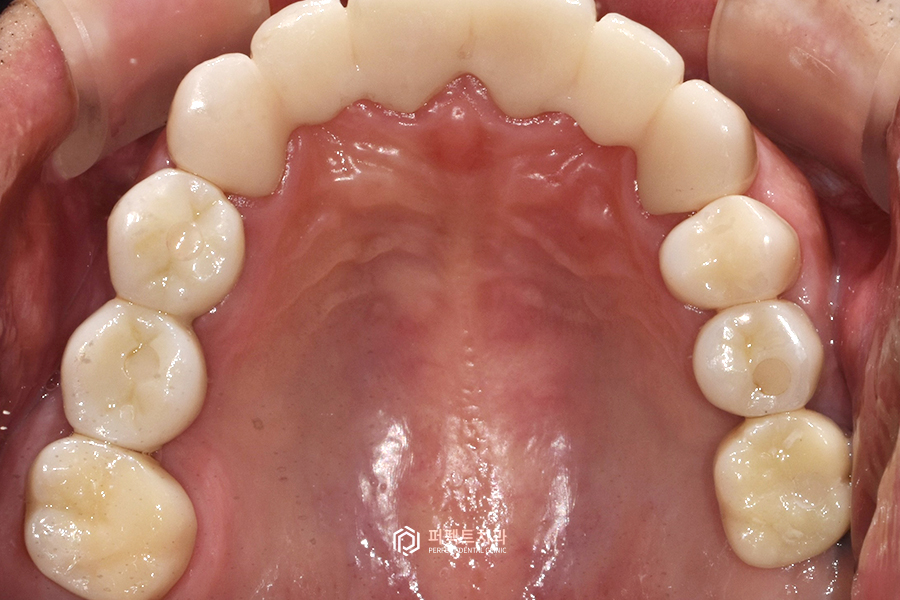

상악 사진을 보시면 뿌리만 남은 치아들과 치아가 없는 부분들을 임플란트로 수복하고, 앞니 보철까지 교체를 해서 윗니 전악 보철 케이스가 된 경우입니다.

치아가 없는 부분은 임플란트로, 기존 보철물은 지르코니아 크라운으로 교체를 해서 윗니는 전체적으로 치아가 다시 완성된 케이스라고 생각을 하시면 될 것 같습니다.